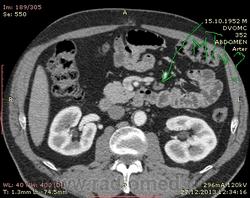

61 год. Рак желудка, в 2011 году субтотальная резекция. Жалоб нет. На вид здоровый, не худой, розоволицый мужик. На УЗИ нашли гиперэхогенное образование в VI сегменте печени 0.8 х 0.6 см. Рекомендовали КТ. Ну и вот: в печени в VI сегменте мелкий кальцинат...больше ничего страшного не вижу. В аорте куча мягких и "твердых" бляшек. Очень интересует Ваше мнение по поводу найденых, как мне кажется, достаточно крупных лимфоузлов...не похожи на метастатическое поражение?

Желудок резецирован по Б-II, лимфоузлы не увеличены. Подпеченочный аппендикс.

и в портальную фазу практически равны по плотности сосудам. Нормальные лимфоузлы всегда гиподенснее сосудов. Форма лимфоузлов может быть любой, и лишь округлость во всех реконструкциях может свидетельствовать о лимфаденопатии. Обычно паракавальный узел крупный и овально-округлый в короналах, но уплощенный на сагитталах, как в вашем случае - нормальный. Не всегда видны жировые ворота лимфоузла. При воспалительной лимфаденопатии узел может быть крупным, "набухшим", при сохранении жировых ворот. Округлый лимфоузел размерами даже меньше нормы в коротком поперечнике, но с патологическим накоплением контраста, считается измененным, и подозрителен на метастаз.

Для информации: симуляция паракавальной лимфаденопатии: